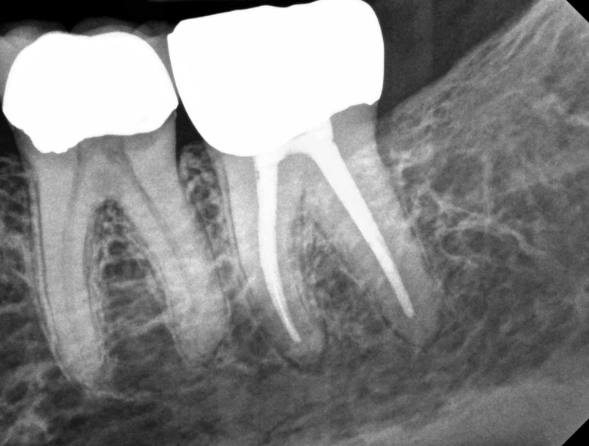

- More Roots and Canals: Front teeth might have one root. A molar can have two, three, or even four roots, each with one or more canals. Finding and cleaning all of them is a precise task.

So, when we talk about root canal on molar teeth, we're talking about a more involved version of the standard procedure. It often requires more time, expertise, and almost always a crown afterward. Which brings us to the next point...

After the canals are cleaned, shaped, and dried, they need to be filled to prevent re-infection. A biocompatible material, usually a rubber-like substance called gutta-percha, is used to fill the space. It's sealed in place with a dental adhesive cement. The goal is to hermetically seal the root canal system.

Step 4: The Temporary Filling and The Essential Crown

The access hole in the top of your tooth is closed with a temporary filling. Now, here's the critical part almost everyone misses: The RCT is only half the battle for a molar.

A molar that has had a root canal is more brittle and prone to fracture because it's no longer alive and hydrated from the inside. Given the immense chewing forces it withstands, leaving it without a crown is like driving a car without a bumper—it might work until the first real impact.

So, the final, non-negotiable step is placing a crown (a "cap") on the tooth. This usually happens in a second appointment, once any initial tenderness has subsided. The crown protects the tooth and restores its full function. The American Dental Association's MouthHealthy site strongly reinforces the need for a crown after a molar RCT to prevent fracture. You can read more about the importance of crowns on their official page here.